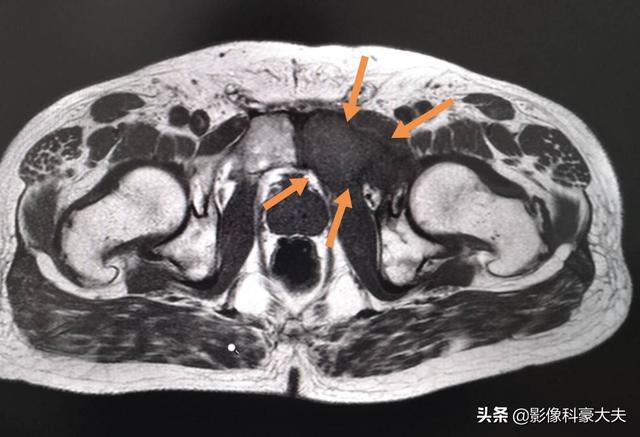

この患者だ。左股関節痛、大腿骨頭壊死を心配したが、肺がん骨転移と判明。